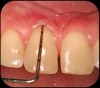

Then, too, are opportunities to prepare the site for regeneration by coupling therapies, applying an enamel matrix derivative, along with traditional bone grafts of demineralized freeze-dried bone allograft; potentially, gains in attachment with minimal probing depth and retained papilla may avoid the need for an implant (Figure 2 through Figure 7).

Severe periodontitis lesion.

Fig. 2

Facial bone loss and a mesial vertical defect.

Fig. 3

Application of enamel matrix derivative.

Fig. 4

Demineralized freeze-dried bone allograft.

Fig. 5

Evidence of clinical attachment gain.

Fig. 6

The 9-year postoperative radiograph.

Fig. 7